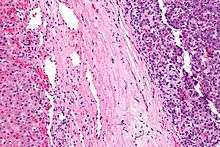

| Micrograph of a hepatoblastoma. H&E stain. | |

Hepatoblastoma is an uncommon malignant liver cancer occurring in infants and children and composed of tissue resembling fetal liver cells, mature liver cells, or bile duct cells. They usually present with an abdominal mass. The disease is most commonly diagnosed during a child's first three years of life.[1] Alpha-fetoprotein (AFP) levels are commonly elevated, but when AFP is not elevated at diagnosis the prognosis is poor.[2]